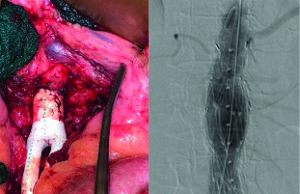

Vascular surgeon Lewis Schwartz, MD, has had an interest in biomedical engineering since very early in his career. So his involvement in the early-stage...